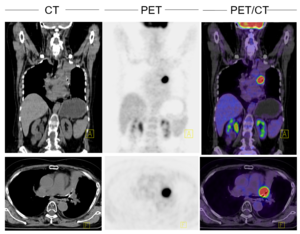

FDG-PET/CT

FDG-PET/CT ist eine funktionelle Diagnostik, die den Zuckerstoffwechsel im Körper darstellt. Die Körperzellen mit erhöhtem Zuckerstoffwechsel (z.B. Tumorzellen) können so bildlich dargestellt werden.

Nach einer Einwirkzeit von 60 min wird die Untersuchung durchgeführt. Während der Untersuchung mit PET-Scanner, die etwa 30 min dauert, müssen Sie ruhig liegen bleiben. In einzelnen Fällen ist eine zweite Aufnahmeserie ohne erneute Injektion nach einer Pause erforderlich. Bei Hirn-PET wird ca. 40 min nach der Injektion von FDG die Bildaufnahme durchgeführt, diese dauert ca. 10 min.